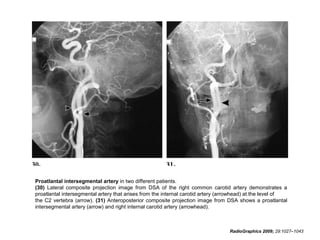

Proatlantal intersegmental artery in two different patients.

(30) Lateral composite projection image from DSA of the right common carotid artery demonstrates a

proatlantal intersegmental artery that arises from the internal carotid artery (arrowhead) at the level of

the C2 vertebra (arrow). (31) Anteroposterior composite projection image from DSA shows a proatlantal

intersegmental artery (arrow) and right internal carotid artery (arrowhead).

Proatlantal intersegmental arteryin two different patients. (30) Lateral composite projection image from DSA of the right common carotid artery demonstrates a proatlantal intersegmental artery that arises from the internal carotid artery (arrowhead) at the level of the C2 vertebra (arrow). (31) Anteroposterior composite projection image from DSA shows a proatlantal intersegmental artery (arrow) and right internal carotid artery (arrowhead). RadioGraphics 2009; 29:1027–1043